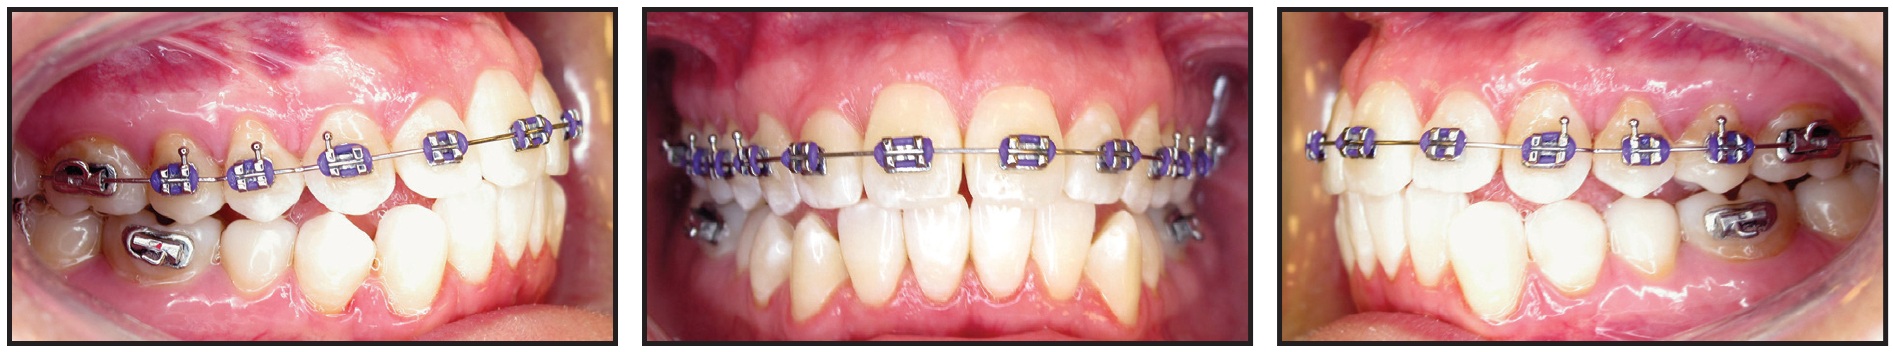

Clinical examination found a slightly convex profile with a fuller right side of the face and asymmetrical commissures (lower on the right). The lower facial third was long, and a dental cant was evident; the chin was positioned slightly to the left of the midsagittal plane. The patient had a Class I occlusion with 2-3mm of crowding in the maxillary arch, 4-5mm of crowding in the mandibular arch, and a canted occlusal plane. The overbite and overjet were normal. A Bolton discrepancy was attributable to excessive tooth size in the mandibular arch. The TMJ complex showed a maximum opening of 45mm with a 10mm range of protrusive, left lateral, and right lateral movements. The right and left external pterygoid muscles were tender on palpation; the left condyle clicked on lateral movements, while the right clicked on opening (Fig. 1B).

Fig. 1 31-year-old female patient with previous TMD treatment, Class I occlusion, Class II skeletal relationship, canted occlusal plane, lower Bolton discrepancy, and 45mm maximum TMJ opening before treatment (continued in next image).

Fig. 1 (cont.) 31-year-old female patient with previous TMD treatment, Class I occlusion, Class II skeletal relationship, canted occlusal plane, lower Bolton discrepancy, and 45mm maximum TMJ opening before treatment.

Cephalometric analysis indicated a Class II skeletal relationship, due to a slightly retrognathic mandible, and a steep mandibular plane. The panoramic radiograph showed parallel roots, previously extracted third molars, and a short ramus on the left side. The right TMJ evidenced remodeling with a posterosuperior loss of volume, thin joint space, posteriorly positioned condyle, and flattened eminence. The left TMJ exhibited inactive degenerative joint disease with a posterosuperior loss of volume, thin joint space, posteriorly positioned and small condyle, flattened eminence, and anterior osteophyte.